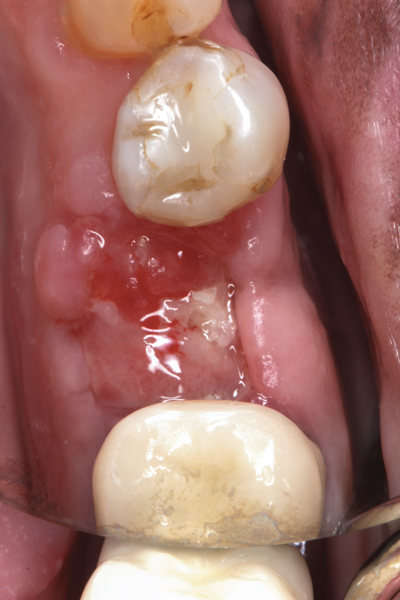

Fig 20. (Case 4) Radiograph of tooth No. 30, which had a hopeless prognosis.

Figure 20

Fig 21. Radiograph of extraction socket. Buccal plate was two-thirds resorbed.

Figure 21

Fig 22. Bone graft was placed in the socket and a d-PTFE barrier was used to cover the graft. The bone graft material was placed beyond the alveolar housing to accommodate shrinkage of graft material and to facilitate attaining a wide alveolar ridge. The barrier was removed after 5 weeks.

Figure 22

Fig 23. Implant inserted in a regenerated ridge after 6 months healing.

Figure 23